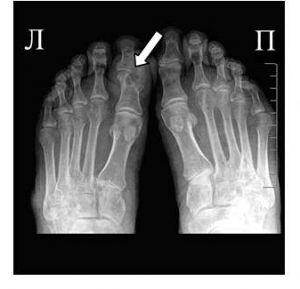

На фото симптом «пробойника» на кости первого пальца ноги

В конце концов, наступает такой момент, когда боль в суставах имеет постоянный характер, а светлые промежутки между приступами практически исчезают. Данное состояние носит название «подагрический статус», или хронический подагрический артрит. При хроническом подагрическом артрите наступает разрушение суставного хряща, а в рядом расположенных костях образуются специфические дефекты — «пробойники», представляющие собой полость, заполненную микрокристаллами урата натрия.

Рентгенография в начале заболевания проводится с целью дифференциальной диагностики с другими артропатиями, специфические же признаки подагры при этом отсутствуют. Только при переходе патологии в хроническую форму на снимках можно увидеть внутрикостные тофусы, краевые эрозии костей.

- Рентгенография. Исследование пораженных суставов определяет развитие тофусов, а также наличие участков с разрушенной суставной и костной тканями;

Субкортикальные кисты без эрозий (при рентгенографии)